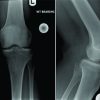

An X-ray of the hand showed a radiopaque mass of 5.0 × 4.5 cm with slight internal calcification on the palmar side of the fifth proximal phalanx, without changes in the bony cortices, additionally lytic image in the proximal third of the middle phalanx of the fifth finger with sclerotic borders, polylobulated pattern, without periosteal or soft tissue reaction (Fig. 2).